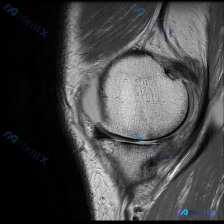

刚整理了一个很有临床意义的病例,核心矛盾是「临床怀疑软骨异常,但现有影像完全正常」,把整个分析思路分享给大家。 病例基础信息 这是一份单张膝关节矢状位T1加权MRI影像,临床提出的核心观察方向是「软骨异常」,无其他临床病史、症状或其他检查资料。 影像具体观察结果 我们先把影像所见说清楚: 1. 骨骼...

看到这个病例挺有代表性的,整理出来和大家分享一下思路。 病例基础信息 这是一张膝关节矢状位T1加权序列MRI影像,用户提出问题:观察图像是否存在软骨异常。 先给大家整理影像评估的基本结果: 1. 骨骼结构:股骨远端、胫骨近端、髌骨皮质连续,骨髓信号未见异常高低信号,关节面形态基本正常 2. 半月板:...

最近遇到一个挺有启发的读片问题,整理出来和大家分享一下: 病例基本情况 这是一份膝关节矢状位T1加权序列MRI,有人提出这份影像可以观察到「软骨异常」,我们先来看详细的影像分析结果: 影像结构整体评估 1. 骨骼结构:股骨远端、胫骨近端、髌骨骨皮质连续,无骨折;骨髓信号正常,无异常低信号提示水肿或占...

今天分享一例膝关节MRI读片的分析思路,问题是:图像里能发现什么异常,和提问提到的「软骨异常」有什么关系? 病例影像基础信息 这是一张膝关节T1加权矢状位MRI图像,对比度良好,显示膝关节前部结构:髌骨、股骨远端滑车、胫骨近端和髌下脂肪垫,左侧为前侧,右侧为后侧,上为头侧下为足侧。 系统性观察结果...

看到这个膝关节读片的病例,整理了完整信息和分析思路分享给大家。 病例基本信息 核心问题:临床怀疑膝关节存在软骨异常,提供单张膝关节矢状位MRI,请分析图像中的明显发现。 影像基础信息 这是一张清晰度良好的膝关节矢状位PD/T2加权MRI,左侧为前(髌骨侧),右侧为后,上方为股骨远端,下方为胫骨近端,...

看到这张膝关节MRI读片的需求,问题是观察到「软骨异常」,我整理了一下完整的病例资料和分析思路,和大家分享讨论。 一、影像基本信息 这是一张膝关节矢状位T1加权MRI影像,图像对比度尚可,解剖结构清晰,无明显运动伪影,层面接近膝关节中间矢状面,完整显示股骨远端、髌骨、膝关节间隙及胫骨近端结构。 二、...

今天整理了一张膝关节MRI的读片分析,这个病例的思路很有代表性,分享给大家。 病例影像基础信息 这是一张膝关节MRI矢状位T1加权像,图像质量良好,对比度清晰,无明显伪影,层面可显示股骨髁、胫骨平台、交叉韧带等核心结构。 系统读片结果 1. 骨与软骨整体情况:股骨远端、胫骨近端骨髓信号均匀,无局灶低...

看到这个有意思的病例,整理一下完整分析思路分享给大家。 病例影像基本信息 这是一张膝关节矢状位T1加权MRI图像,扫描范围覆盖髌股关节及部分胫股关节,图像对比度良好,可以清晰分辨解剖结构。 我们先按系统读片流程一步步来: 1. 骨骼与对线:股骨远端、胫骨近端、髌骨骨皮质连续,没有明显骨折线;骨髓信号...

刚整理了一份有意思的影像读片病例,和大家分享一下思路。 病例基本信息 本次仅提供放射影像-膝盖MRI-T1序列-矢状位单张图像,核心问题是询问图像中是否存在半月板异常。 影像学读片结果 我仔细读了这张片子,所有结构的情况如下: 1. 骨骼结构:股骨远端、胫骨近端、髌骨的骨皮质连续,骨髓信号正常,没有...

刚整理了一份有意思的膝关节MRI读片病例,核心问题是单张T1矢状位图像提示「软骨异常」,这里把整个分析思路整理出来和大家交流。 一、病例基本影像信息 这是一张膝关节正中偏内侧矢状位的T1加权MRI图像,图像质量良好,无明显伪影,可清晰观察髌骨、股骨远端、胫骨近端、后交叉韧带及半月板结构。 二、系统性...